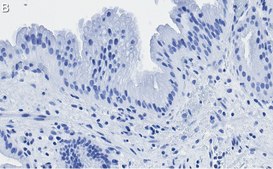

Immunohistochemistry (Paraffin) Analysis: A 1:100 dilution from a representative lot detected Nrf2 in human gallbladder and human cervical cancer tissue sections.